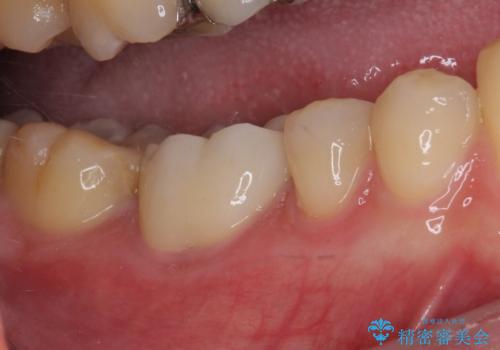

咬合力が強いため、強化セラミッククラウンでの補綴治療を行うこととしました。

強化セラミッククラウンは単一素材のため、非常に高強度でありますが色調は単調なものとなり、隣在歯と調和させることは困難です。